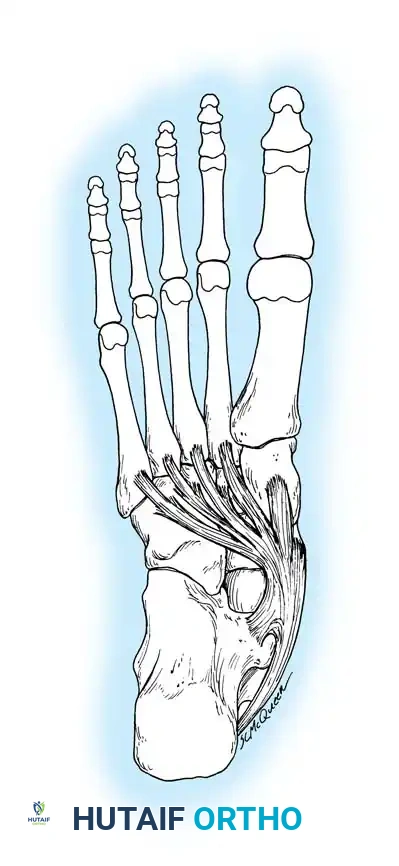

لفهم طبيعة القدم المسطحة الصلبة، يجب أولاً إلقاء نظرة مبسطة على تشريح القدم. تتكون القدم البشرية من مجموعة معقدة من العظام، المفاصل، الأربطة، والأوتار التي تعمل معاً بتناغم لتشكيل "قوس القدم" الطولي. هذا القوس يعمل كممتص للصدمات ويساعد في توزيع وزن الجسم أثناء المشي والركض.

في الحالة الطبيعية، تتحرك عظام الجزء الخلفي والأوسط من القدم (مثل عظمة الكاحل، وعظمة العقب، والعظمة الزورقية) بحرية لتتكيف مع الأسطح المختلفة. ولكن في حالة القدم المسطحة الصلبة، يحدث تقييد شديد أو انعدام كامل لهذه الحركة، مما يؤدي إلى تصلب القدم وفقدان القوس الطبيعي بشكل دائم، سواء أثناء الوقوف أو الجلوس.

التحام عظام الرصغ هو عيب خلقي يحدث أثناء تطور الجنين، حيث تفشل الأنسجة الجنينية في الانفصال لتكوين مفاصل طبيعية بين عظام القدم. بدلاً من ذلك، يتكون جسر غير طبيعي (قد يكون عظمياً، غضروفياً، أو ليفياً) يربط بين عظمتين أو أكثر، مما يمنع الحركة الطبيعية للمفصل.

* التحام العقب والزورقي (Calcaneonavicular Coalition): جسر يربط بين عظمة الكعب (العقب) والعظمة الزورقية.

* التحام الكاحل والعقب (Talocalcaneal Coalition): جسر يربط بين عظمة الكاحل وعظمة الكعب، وغالباً ما يحدث في المفصل الأوسط.